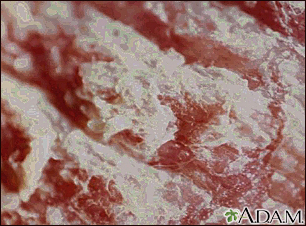

Psoriasis - magnified x4BackPsoriasis - magnified x4This picture shows a 400% magnification of psoriasis. The whitish scales give the silvery appearance to the typical psoriasis lesion. E-mail FormEmail ResultsName:Email address:Recipients Name:Recipients address:Message: